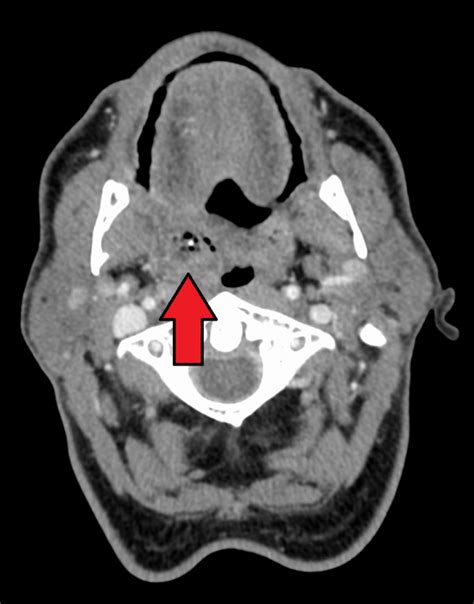

From a medical journal perspective, PTAs are polymicrobial infections, meaning they involve a mix of different bacteria. The usual suspects include Streptococcus pyogenes (the same bacteria that causes strep throat), Staphylococcus aureus , and various anaerobic bacteria. These little buggers team up to cause inflammation and pus formation, leading to that painful abscess. Diagnosing a PTA typically involves a physical exam, where a doctor will look for swelling and redness around the tonsils. They might also feel for a fluctuant mass, which is a fancy way of saying a squishy, pus-filled lump. In some cases, imaging tests like a CT scan might be necessary to confirm the diagnosis and rule out other issues.

- Imaging Tests: In some cases, imaging tests like a CT scan may be necessary. This is especially true if the diagnosis is unclear or if there are concerns about the infection spreading.